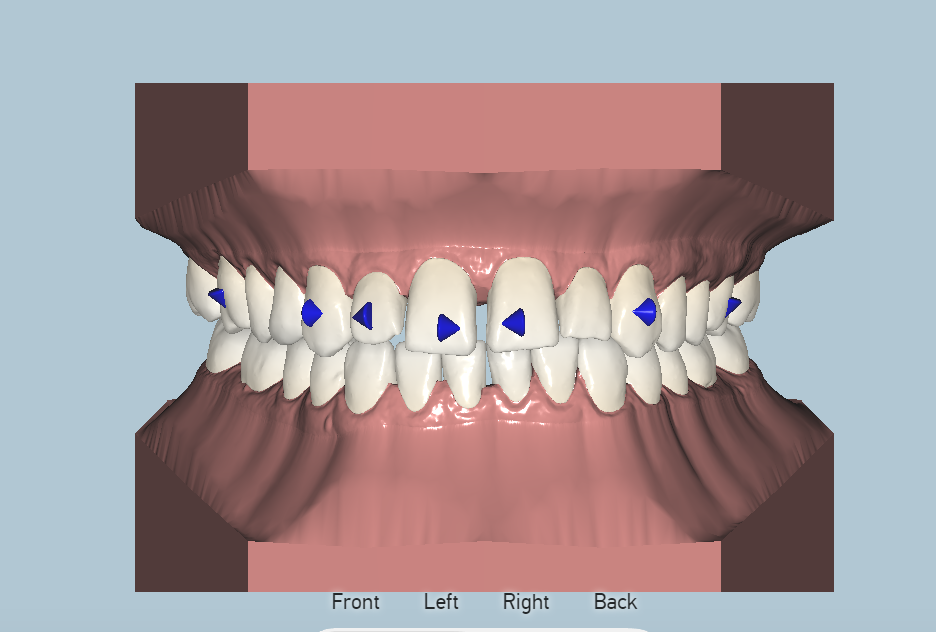

Orthodontist Proposal

After all materials are gathered, an orthodontist creates the movement proposal for the doctors approval. This is done through an on-line link that can be viewed in each stage of the process in 3D. Changes can be requested as needed or the proposal is approved for production.

Placeholder Picture